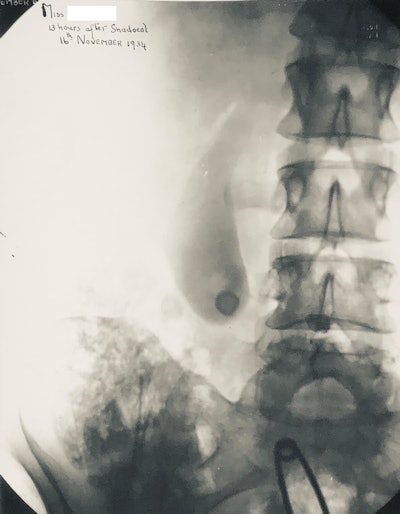

Oral cholecystogram from 1934 showing opacified gallbladder. The technique has now been replaced by ultrasound.

Oral cholecystogram from 1934 showing opacified gallbladder. The technique has now been replaced by ultrasound.The history of contrast media is complex and interesting, and it was fully reviewed by Christoph de Haën in what is now the definitive history of the development of contrast media.2